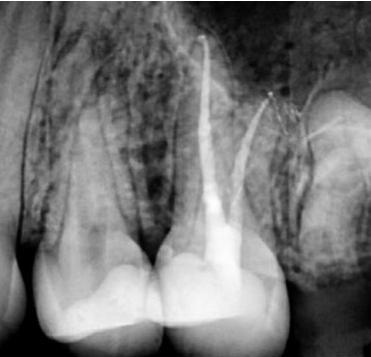

Case 2: A 52-year-old female referred to the clinic for the treatment of tooth 21. Intra-oral examination showed a poor restoration on tooth 21. Percussion and palpation were negative with mobility grade 1. Radiographic examination showed an unsatisfactory restauration on tooth 21 with an apical radiolucency. After obtaining the written consent, the treatment was carried out. The area was anesthetized. Tooth was isolated using the rubber dam and access cavity was opened.

The root canal used for shaping was the EdgeTaper Blaze Utopia to size F2 #25. The final irrigation protocol was performed by a continuous delivery of EDTA and NaOCl. Solutions were activated using ultrasonic activation - 1 minute per solution. Canals were dried and obturated using hydraulic condensation with EdgeBioCeramic Sealer (EdgeEndo).

Lateral and secondary canals are visible on the post operative radiograph.